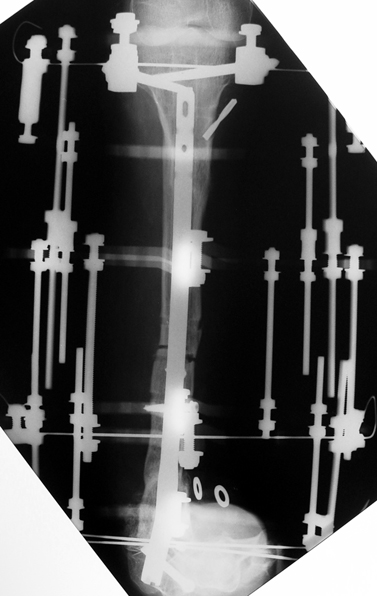

3. POSTTRAUMATIC LOWER LIMB SHORTNESS (MALUNION)

This type of shortness occurs after a fracture heals in a shortened position. Most cases are seen in adults and can be treated with one lengthening operation. Additional deformities can be corrected simultaneously. Most of these cases can be treated with lengthening over nail or just corrections and intramedullary nailing.